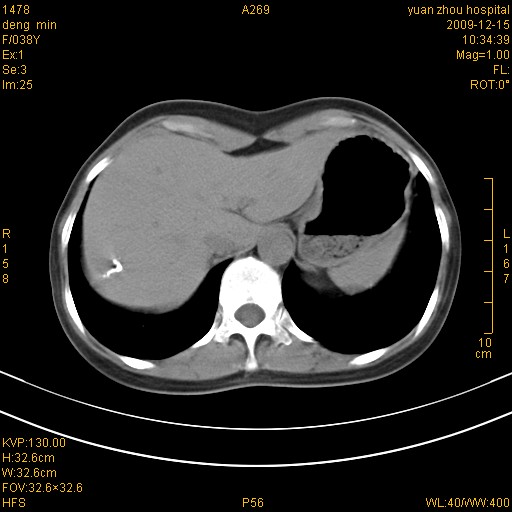

标题: CT23919:F38Y 咳嗽月余 [打印本页]

标题: CT23919:F38Y 咳嗽月余

右肺中下叶、左肺上叶舌段及左肺下叶支气管扩张合并感染。